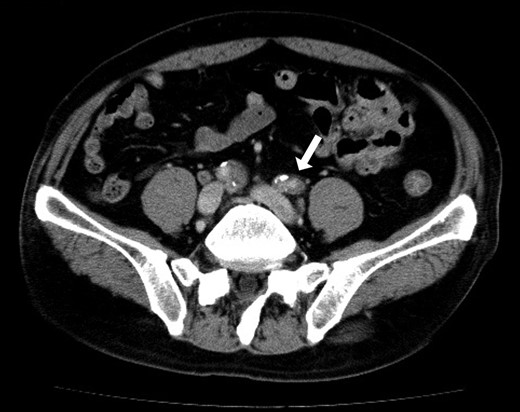

A 70-year-old man underwent a colonoscopy after having episodes of bright red stool per rectum and diarrhea. A lower rectal cancer was diagnosed based on a histology obtained through a biopsy of the rectal lesions (Rb, T2N0M0 cStageI (UICC Classification, 7th ed)). The past medical history was notable for hypertension untreated and smoking 50 pack year. His height was 173 cm, and weight was 73 kg with body mass index of 24.4. The creatinine clearance was 87 ml/min. Although the preoperative history talking failed to recognize the symptoms of intermittent claudication and sensory impairment of his lower extremities, a preoperative contrast enhanced computed tomography (CT) scan demonstrated a significant stenosis in bilateral external iliac artery due to arteriosclerosis obliterans (ASO) (Fig. 1) and occlusions of bilateral internal iliac artery. There was no coagulation abnormality in his blood test or atrial fibrillation on an electrocardiogram.

Preoperative abdominal CT showed bilateral iliac arterial stenosis to 5 mm diameter with calcification (the arrows). Internal iliac arteries had been obstructed bilaterally.